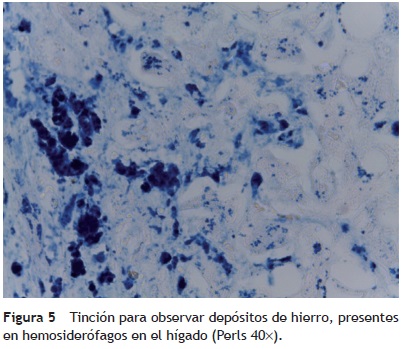

Se encontraron 35 ml de sangre en el hemitórax izquierdo y 25 ml en el pericardio, además de una hemorragia mediastinal. Los cortes histológicos del mediastino mostraron tejido adiposo con hemorragia extensa, restos del timo con corpúsculos de Hassall calcificados y depleción linfoide. Continuando con el mediastino, el corazón tuvo un peso de 100 g vs 115 g. Lo que llamó la atención, desde el punto de vista macroscópico fue una hemorragia petequial en el pericardio, en la aurícula y ventrículos derechos. Visto por su cara posterior se observó la hemorragia en la adventicia de la arteria pulmonar y una hemorragia subepicárdica de 3 × 2 cm. Los cortes histológicos mostraron cardiomiocitos con citoplasma vacuolado, algunos con ligero aumento en el tamaño del núcleo. Esto resulta importante porque la paciente había recibido daunorrubicina, que es cardiotóxico. Sin embargo, no hay cambios histológicos secundarios a la administración de este fármaco. El hígado tuvo un peso esperado de 1600 g contra un esperado de 756 g. Macroscópicamente, se observó un color café claro; histológicamente se observaron muchos cambios, como alteraciones importantes en la arquitectura por la presencia de fibrosis a nivel de las venas centrales, principalmente. A nivel de los espacios porta y de las venas centrales se observaron numerosos hemosiderófagos. En el lobulillo hay esteatosis, y en los sinusoides, también numerosos hemosiderofágos (fig. 4). En el lobulillo, la esteatosis es macro y microvesicular. Estos son datos importantes en la lesión por medicamentos que, al parecer, es lo que se observa en el hígado. La presencia de esteatosis macrovesicular es secundaria a esteroides, y la presencia de esteatosis microvesicular es secundaria a la administración de metrotexate y L-asparaginasa. La fibrosis y el daño que vemos en los espacios porta son secundarios al depósito de hemosiderina tan extenso en esta paciente; además, hay colestasis intracitoplasmática. Se realizó una tinción de Masson donde puede observarse la presencia de puentes de fibrosis, que unen las venas centrales con los espacios porta, dato de lesión irreversible que probablemente progresaría a cirrosis. A mayor aumento es evidente el depósito de colágena IV y VI y la expansión importante a nivel de los espacios porta y de las venas centrales. En una tinción de Perls, específica para ver depósitos de hierro, se puede ver la presencia de hemosiderófagos, con distribución en gránulos gruesos en todos los campos (fig. 5). Resulta importante porque, con base en esto, se realiza la gradificación histológica. Este es un grado IV/IV en la escala de Krause, con presencia de hemosiderina en todos los campos con distribución en gránulos gruesos.

• Hemosiderosis grado IV/IV de Krause.